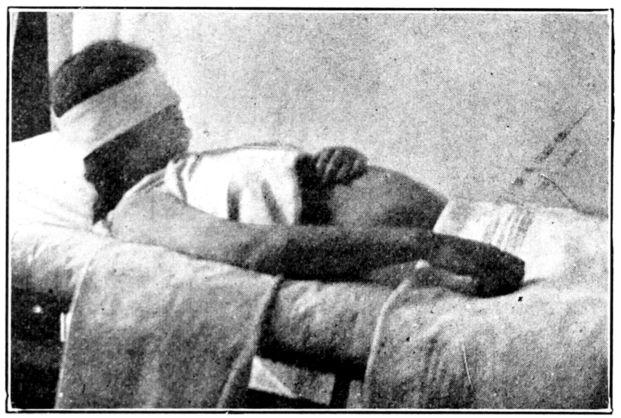

| 41. | Elevated Sims position | 139 |

| 129, 130, 131, 132, 133, 134, 135. | Bed exercises taken during the puerperium | 350 to 353 |